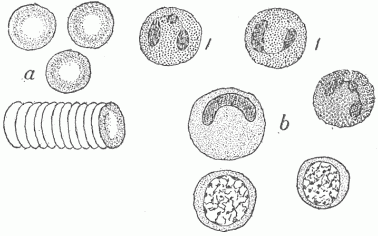

Fig. 12.—The Various Cells In The Blood. (a) The red blood cells, single and forming a roll by adhering to one another; (b) different forms of the white blood cells; those marked "1" are the most numerous and are phagocytic for bacteria.

The blood consists of a fluid, the blood plasma, in which numerous cells are contained. The most numerous of these are small cup-shaped cells which contain a substance called hæmoglobin, to which the red color of the blood is due. There are five million of these cells in a cubic millimeter (a millimeter is .03937 of an inch), giving a total number for the average adult of twenty-five trillion. The surface area of all these, each being one thirty-three hundredth of an inch in diameter, is about thirty-three hundred square yards. The hæmoglobin which they contain combines in the lungs with the oxygen in the inspired air, and they give up this indispensable substance to the cells everywhere in the body. There are also eight thousand leucocytes or colorless cells in a cubic millimeter of blood, this giving a total number of four billion in the average adult, and these vary in character and in relative numbers (Fig. 12). The most numerous of these are round and slightly larger than the red cells; they have a nucleus of peculiar shape and contain granules of a definite character. These cells serve an important part in infectious diseases in devouring and destroying parasites. They have power of active independent motion and somewhat resemble certain of the free living unicellular organisms. The blood plasma, when taken from the vessels, clots or passes from a fluid into a gelatinous or semi-solid condition, which is due to the formation within it of a network of fine threads termed fibrin. It is by means of the clotting of the blood that the escape of blood from ruptured vessels is arrested.